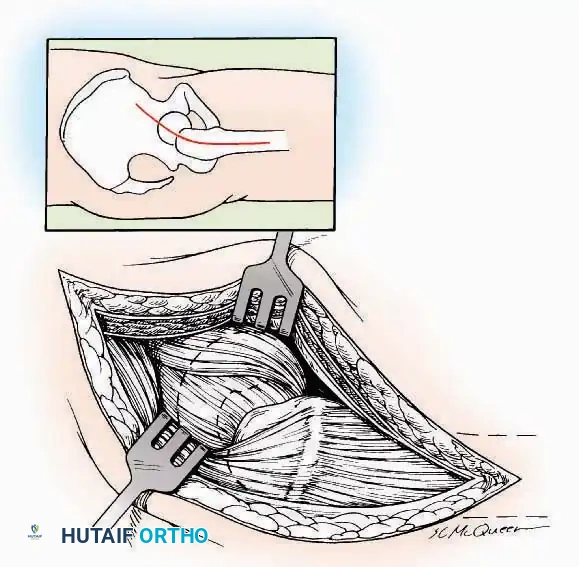

Anterior Approach

Indications: Total ankle arthroplasty (TAA), anterior ankle arthrodesis, and excision of anterior tibial/talar osteophytes (anterior impingement).

💡 Clinical Pearl

Gaining access to the medial gutter (the articulation between the medial malleolus and the medial articular facet of the talus) can be challenging through a pure anterior approach. Meticulous medial subperiosteal dissection of the joint capsule is required to avoid excessive traction on the anterior neurovascular bundle.

Surgical Technique:

* Incision: Make a 10 to 15 cm longitudinal incision over the anterior aspect of the ankle, centered exactly midway between the medial and lateral malleoli.

* Superficial Dissection: Incise the superficial fascia. Identify and protect the superficial peroneal nerve branches laterally and the saphenous nerve medially.

* Internervous Plane: The deep dissection exploits the plane between the Extensor Hallucis Longus (EHL) tendon (innervated by the deep peroneal nerve) and the Extensor Digitorum Longus (EDL) tendons (also innervated by the deep peroneal nerve).

* Neurovascular Bundle: Incise the extensor retinaculum. Carefully identify the anterior tibial artery and the deep peroneal nerve, which typically lie between the EHL and EDL, or directly deep to the EHL. Retract the neurovascular bundle laterally with the EDL, or medially with the EHL, depending on the specific anatomical variant encountered (lateral retraction is most common).

* Capsulotomy: Incise the anterior joint capsule longitudinally. Elevate the capsule subperiosteally from the anterior tibia and the talar neck to expose the entire tibiotalar articulation.